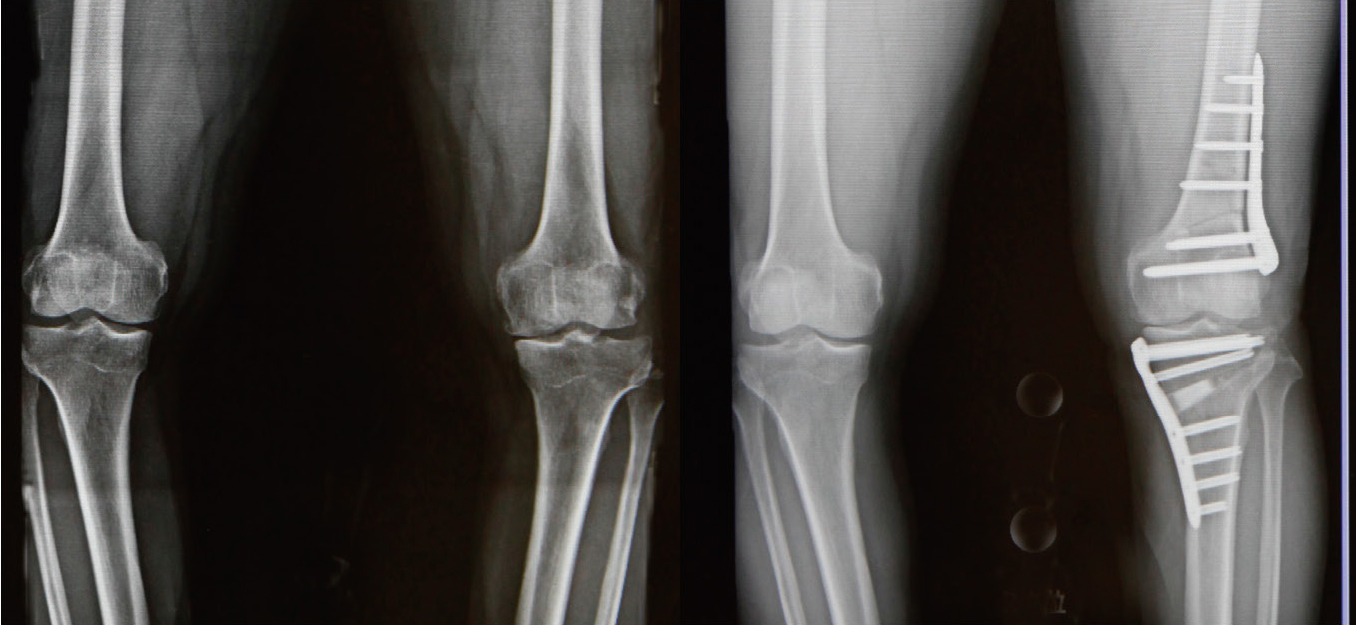

骨切り術

手術前と手術後のレントゲン

骨切り術は、軟骨のすり減りや変形が膝関節の内側だけ、もしくは外側だけに限局している場合に適応となります。特に多いのは、すり減りが内側に大きくO脚になっている人です。

骨切り術にはいくつか種類があり、これまで一般的に行われてきたのは、「高位脛骨骨切り術(HTO)」といって、脛骨(すねの骨)の上の方を切って角度を矯正する方法です。

最近は、より患者さんの状態に合わせた骨切り術が行われるようになってきました。例えば、脛骨の内側から外側に向かって骨を切り、内側を開いて矯正する「内側開大式高位脛骨骨切り術(OWHTO)」、脛骨と大腿骨(太ももの骨)の両方の骨切りを同時に行い、できる限り正常な状態へと改善する「ダブルレベルオステオトミー(DLO)」、膝蓋骨の位置を保つことで術後の軟骨損傷の発症リスクを減らす内側開大式脛骨粗面下骨切り術(DTO)などがあります。

…このように、新しい骨切り術の方式が開発されていることによって、これまでは、人工膝関節しか選択肢がなかった人が骨切り術で治療を受けられ、自分の膝を残しながら元の生活に戻ることも可能です。

人工膝関節置換術

人工膝関節置換術は、変形性膝関節症や関節リウマチなどによって傷んだ膝関節の表面を、人工の関節部品(インプラント)に置き換える手術です。痛みの軽減や歩行能力の改善を目的として行われます。

手術では、大腿骨や脛骨(必要に応じて膝蓋骨)の骨の表面を整え、金属やポリエチレンなどでできた人工関節を設置し、骨セメントなどを用いて固定します。これにより、関節の動きをなめらかにし、日常生活動作の改善を目指します。